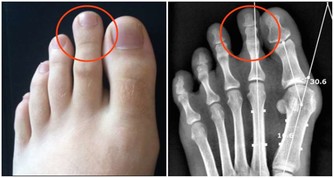

另外,長在手掌、腳底、腰部​周圍、腹股溝、腋下等部位的痣也會更危險,因為這些部位更容易被摩擦,在長期的刺激下痣容易發生破損、潰爛等,惡變的可能性也就更大。如果是這些部位的痣,建議及時到醫院切除。